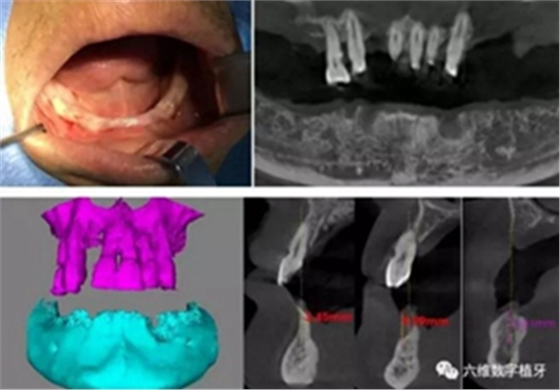

患者男,喜歡抽煙喝茶,有重度牙周病,下頜的牙齒已經(jīng)完全拔除,上頜牙齒在CT中可見,牙槽骨吸收很嚴(yán)重,牙根部分暴露,粘膜萎縮。要求:進(jìn)行下半口固定義齒即刻修復(fù)。

從CT可以看出患者前牙區(qū)牙槽骨非常薄,有的地方3.5mm不到,左側(cè)4號(hào)牙位有嚴(yán)重的骨吸收,需要進(jìn)行植骨,后牙區(qū)離神經(jīng)管較近,設(shè)計(jì)種植短粗型種植體。

導(dǎo)航手術(shù)過程照片

通過術(shù)前精確的設(shè)計(jì),避開了患者骨壁較薄需要做骨劈開的區(qū)域,避免了大翻瓣造成較大創(chuàng)傷,大大提高了患者的舒適度。